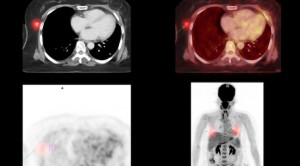

Peran Pemeriksaan Kedokteran Nuklir dalam Penyakit Tuberkulosis

Pemeriksaan kedokteran nuklir bermanfaat untuk mendeteksi proses infeksi atau inflamasi di tahap awal/dini, sehingga dapat berperan dalam diagnosis penyakit tuberkulosis. Seperti diketahui,...(Baca Selengkapnya)